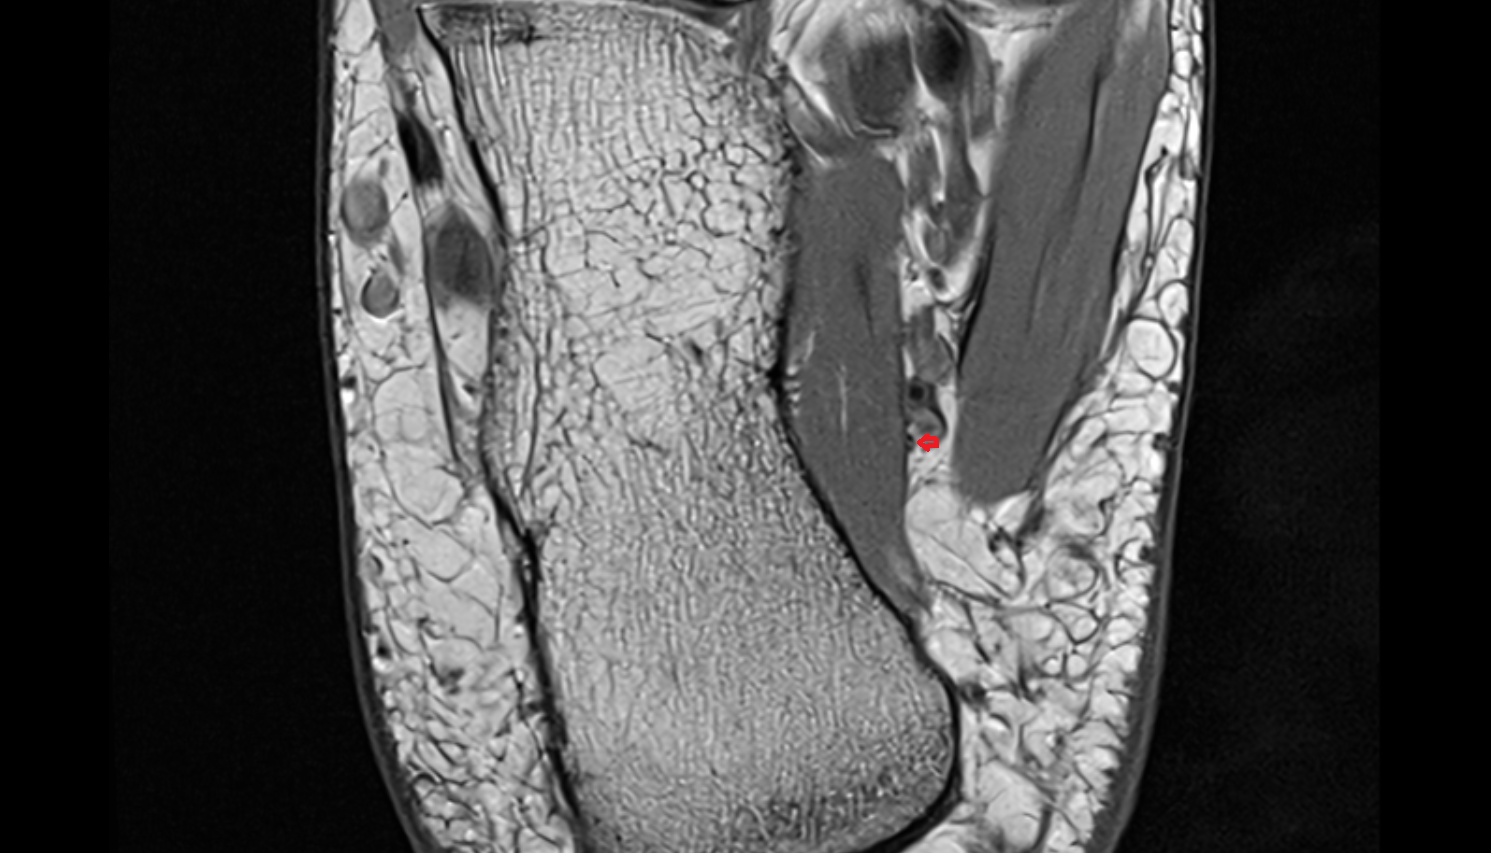

MRI images

Inferior calcaneal nerve (Baxter’s nerve) axial cross sectional anatomy 3T MRI AI enhanced radiology image-img-00000-00000_00001